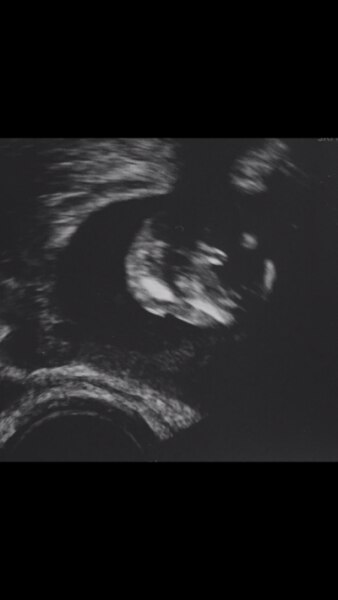

Foto ist aus der Perspektive von hinten unten ist der Unterschenkel und ein Bein man schaut quasi von hinten auf den Pops -:) was sagt ihr ?

Ich sehe ein Mädchen. Aber in der 15 SSW ist dies ja noch nicht wirklich aussagekräftig.

Tippe auch auf Mädchen!

Ja das stimmt ist noch früh obwohl ich es bei meinem Sohn schon in der 13 deutlich sehen konnte Mein Arzt sagte in der 13 Tendenz Mädchen jetzt musste ich aufgrund Bauch weh ins kh da sagte man dann eher junge aber ehrlich gesagt sehe ich eher einen Schlitz -:) bin da etwas verwirrt

Mädchen